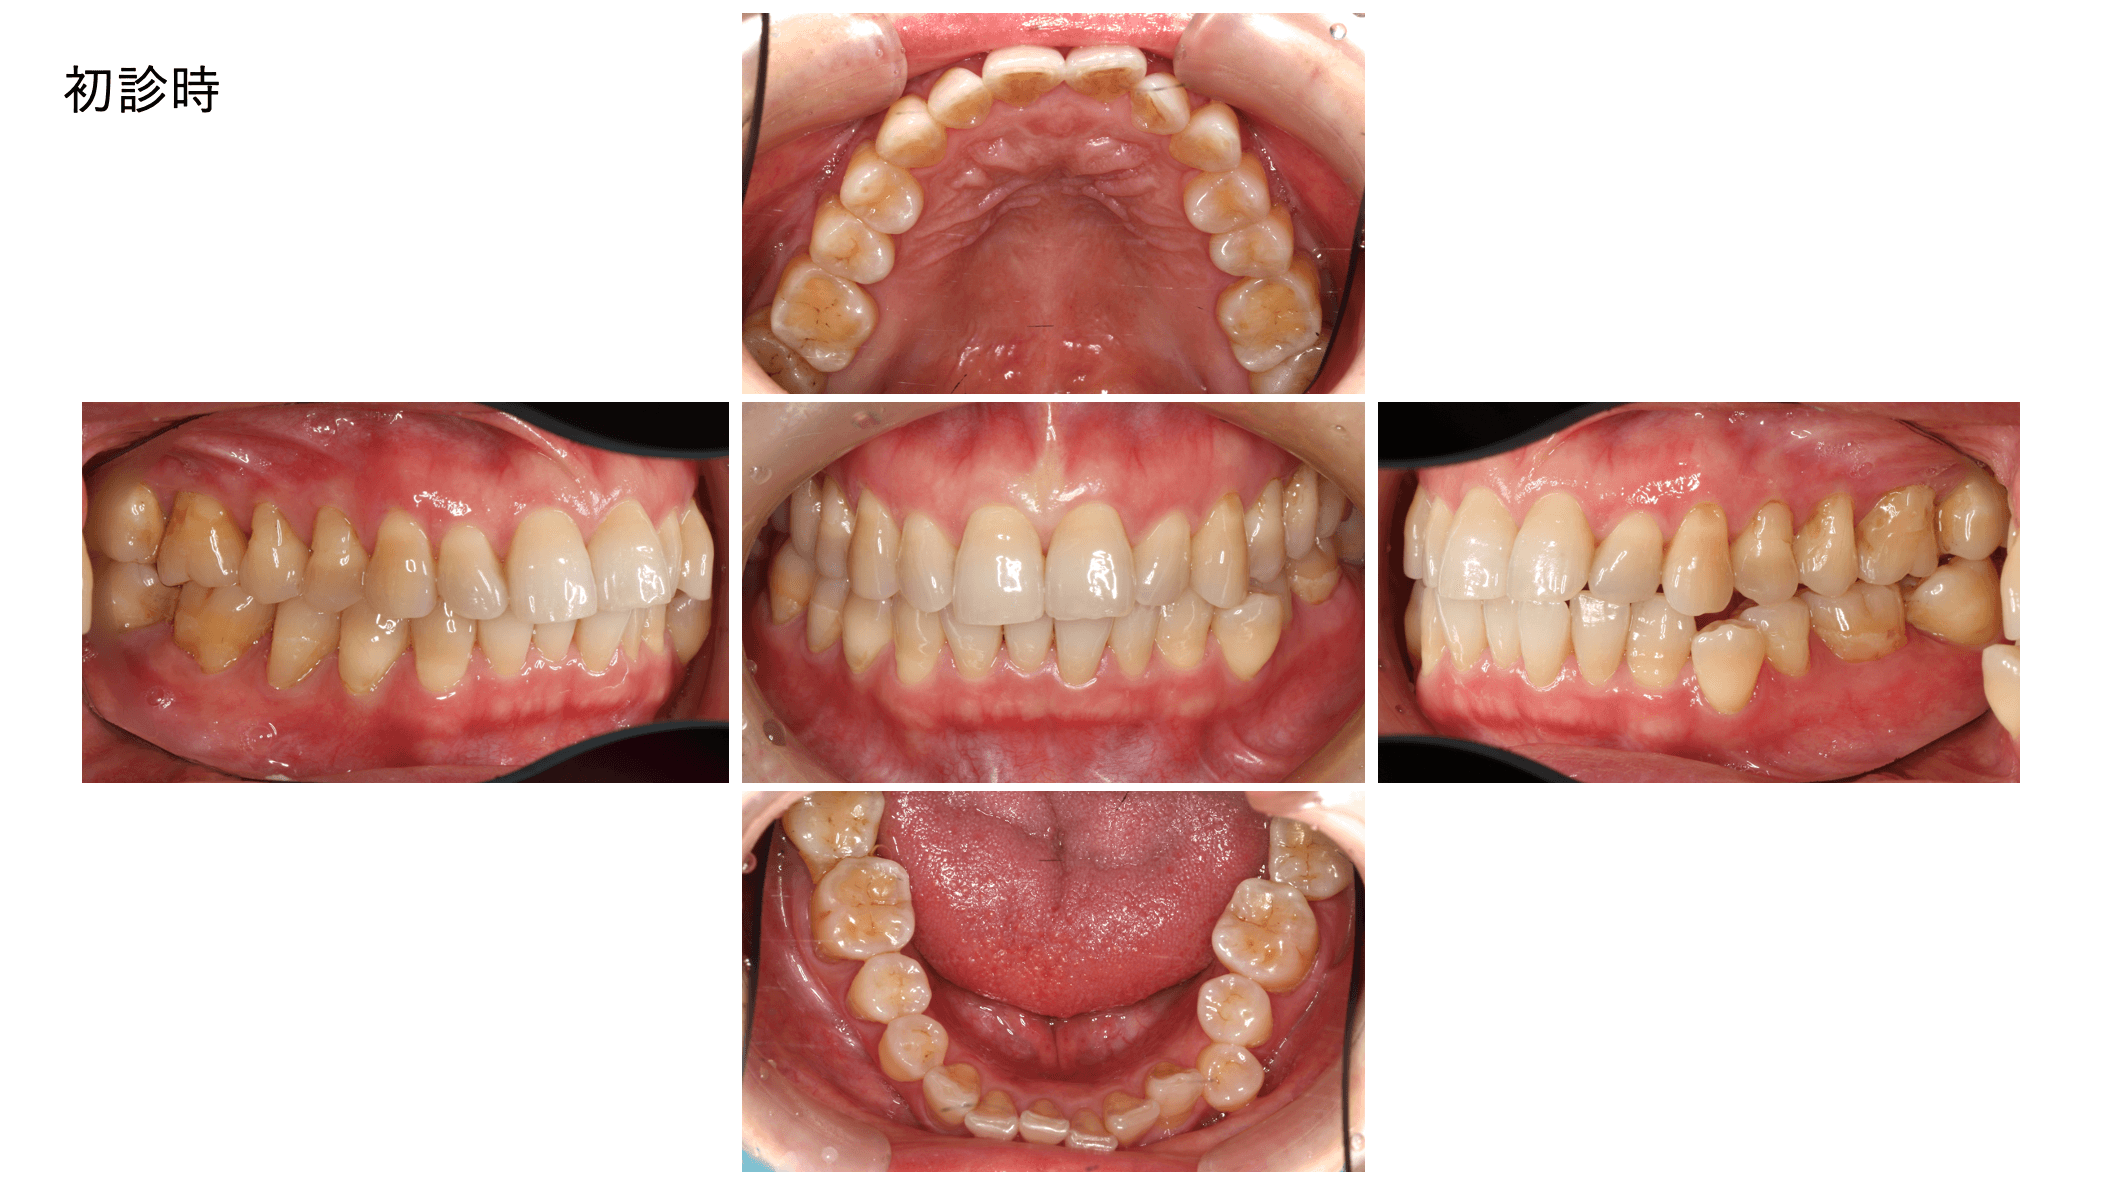

お口の中は全体的に良好な状態に見えましたが、下の奥歯に「限局型慢性歯周炎(ステージ3 グレードC)」が判明し保存が極めて難しい状態に。ここから歯周組織再生療法による回復を試みました。

44歳の女性、歯が揺れているという理由で心配になりご来院されました。PC(プラークコントロール)はそこまで悪くなく、全顎的な歯肉炎もありません。オーバーブラッシングによる歯肉退縮が若干みられます。

見た目では歯根露出が大きい程度の印象しかない。